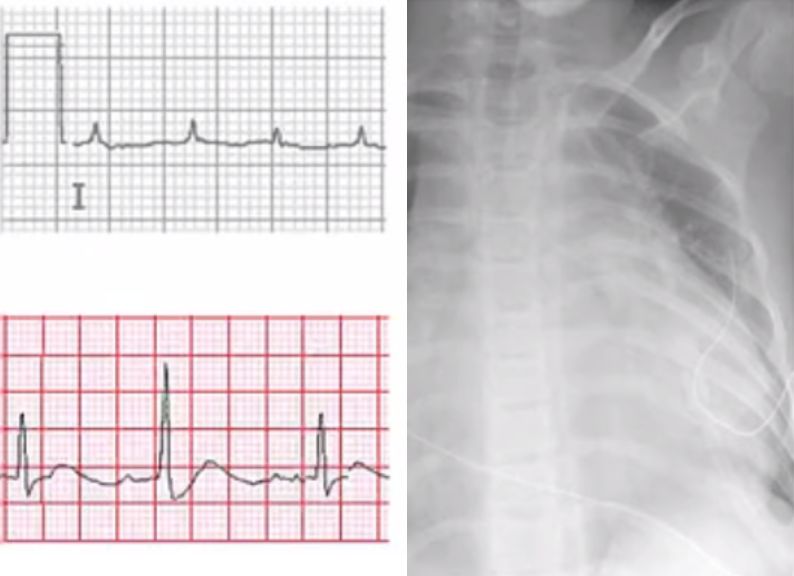

最近,在网上看到一个PCI后出现大量心包积液、穿刺不成功误入右心室的病例报道,穿刺针穿刺失败,动用了猪尾导管才算搞定。于是想起自己在心内科做见习医师时主管的一名患者,PCI术后3天,在出院前夕出现心包填塞,紧急心包穿刺时出现心跳骤停后复苏不成功死亡。一直忘不了老太太惨白的脸,心有余悸。

还没当成心内科主治医就跑急诊去了,在急诊也没遇到穿刺的机会。对于心包穿刺,一直还停留住院医期间远远看着上级医师操作的阶段。十几年前,便携式超声还没有那么普及,基本上都是盲穿。印象中,上级医生强调的就是两点:位置、方向,剩下的也许就只能靠感觉了。

心包穿刺术正式开始了

穿刺术后监测